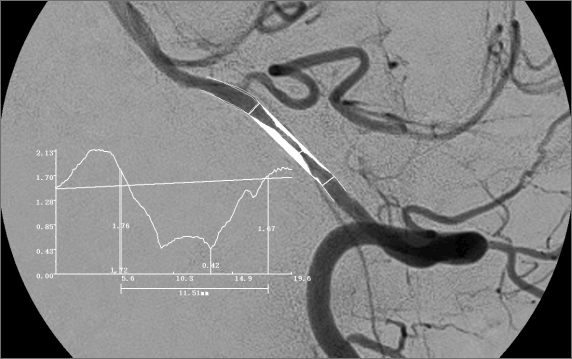

脑血管造影定性和定量分析(DSA)

- 脑血管疾病的定性诊断

- 狭窄部位,及狭窄长度的测定

- 最狭窄管腔直径及参考管腔直径的测定

- 介入治疗后残余狭窄及参考管腔直径的测定